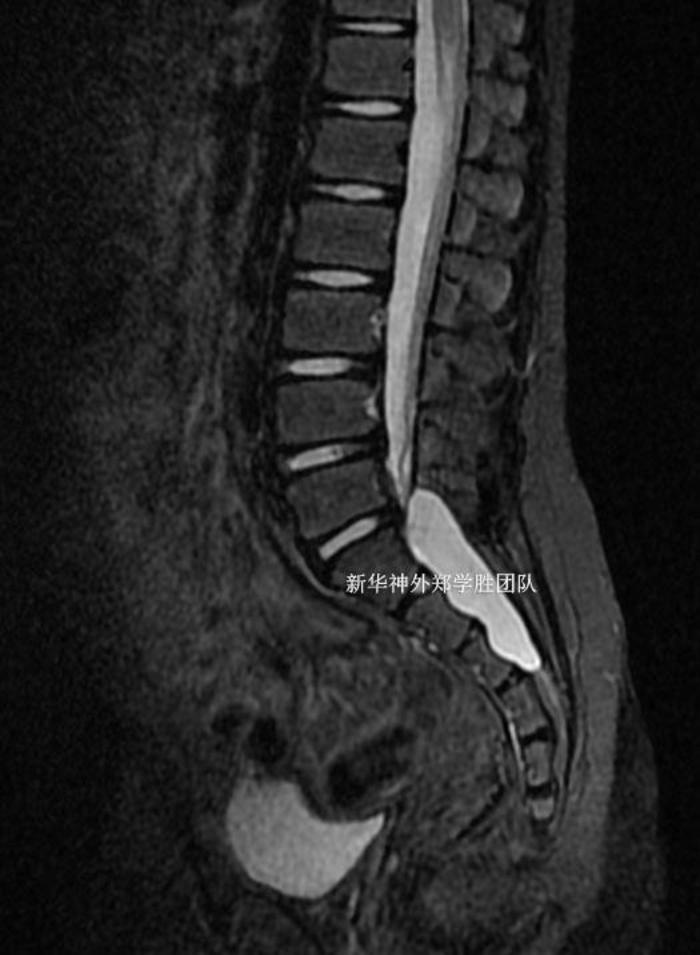

术后复查磁共振,骶管囊肿完全封堵。手术切口仅4厘米,患儿术后几乎没有什么疼痛,两周下床活动自如,治愈出院。没有任何神经功能障碍。